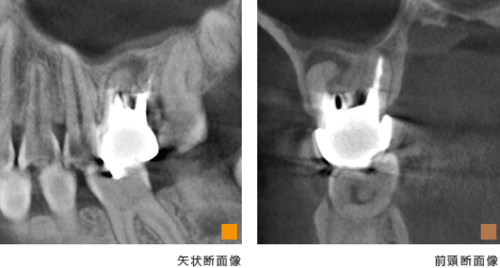

根管治療とCT

歯根の先端の病巣発見や、治療後の治癒の状態など、正確に把握できます。

歯科用CT画像を使った正確な診断によって、根の病気の完治を目指しやすくなります。